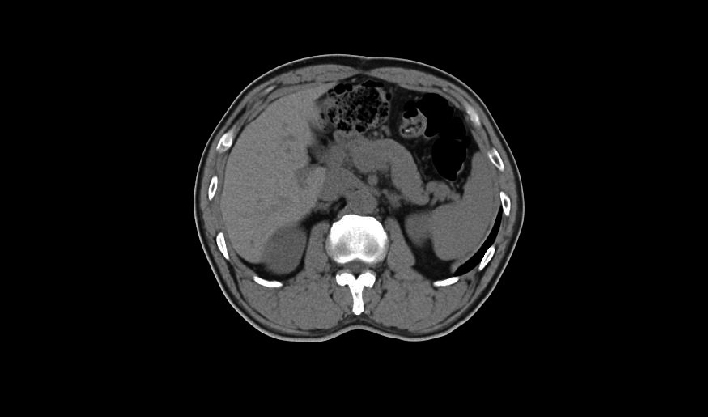

El detector de cuerpo ancho de cuarta generación, de desarrollo propio, cubre más áreas de tejido.

La matriz de reconstrucción de 1024*1024 amplía los datos de la imagen cuatro veces. Combinado con imágenes de corte fina, incluso las lesiones más invisibles son claramente visibles.